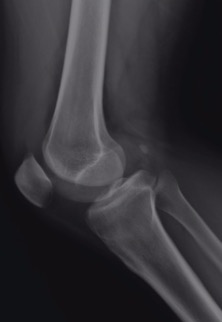

肌肉骨骼系统读片基础

X线的应用价值与限度骨骼组织密度较高,与周围软组织具有良好的对比度,而其本身的骨皮质、骨松质和骨髓腔之间亦有足够的对比度,因此X线片具有较高的空间分辨率和一定的密度分辨率,至今仍是骨骼疾病的重要和首选检查方法。X线片可发现疾病,显示疾病范围、程度,并结合相关临床表现和实验室检查,对特征性的外伤、感染.....